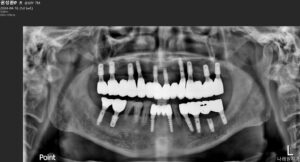

모든 치료가 마무리된

파노라마 사진과

구강 내 사진인데요.

환자분께서는

치료 전에는 식사가 힘드시다 보니

소화도 잘되지 않아 불편감이 많으셨는데,

치료 후에는 양측 저작이 편안하게 잘 되고

심미성도 높아져

대화를 하거나 웃을 때

입을 가리지 않아도 되어 만족해하셨습니다.